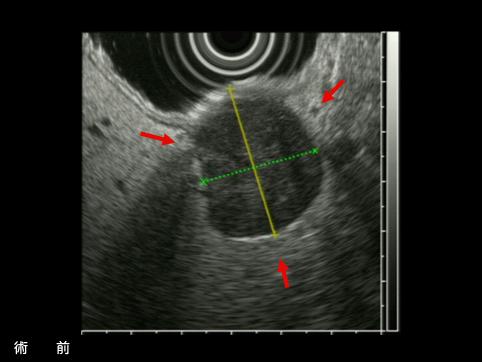

A case of gastrointestinal stromal tumor that extraluminally developed in size during four years and ten months.

[Image-ID:11339]

악성 비상피성종양/평활근육종

위(부위)/체부

검사방법

초음파

종양의 최대경(밀리미터)

25~29